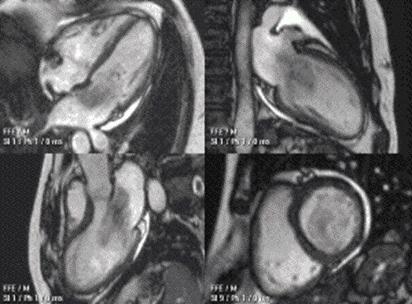

AI in cardiovascular research EDITORS' NOTE

Readers can explore topics such as United Readers can explore topics such as United NationsSustainableDevelopmentGoals,howAI NationsSustainableDevelopmentGoals,howAI isusedinthecardiovascularresearchfield,how isusedinthecardiovascularresearchfield,how physiology, portrayed in film, can be used in physiology, portrayed in film, can be used in physiology education along with the ethical physiology education along with the ethical implications of recreational drug use on male implications of recreational drug use on male fertility. fertility.